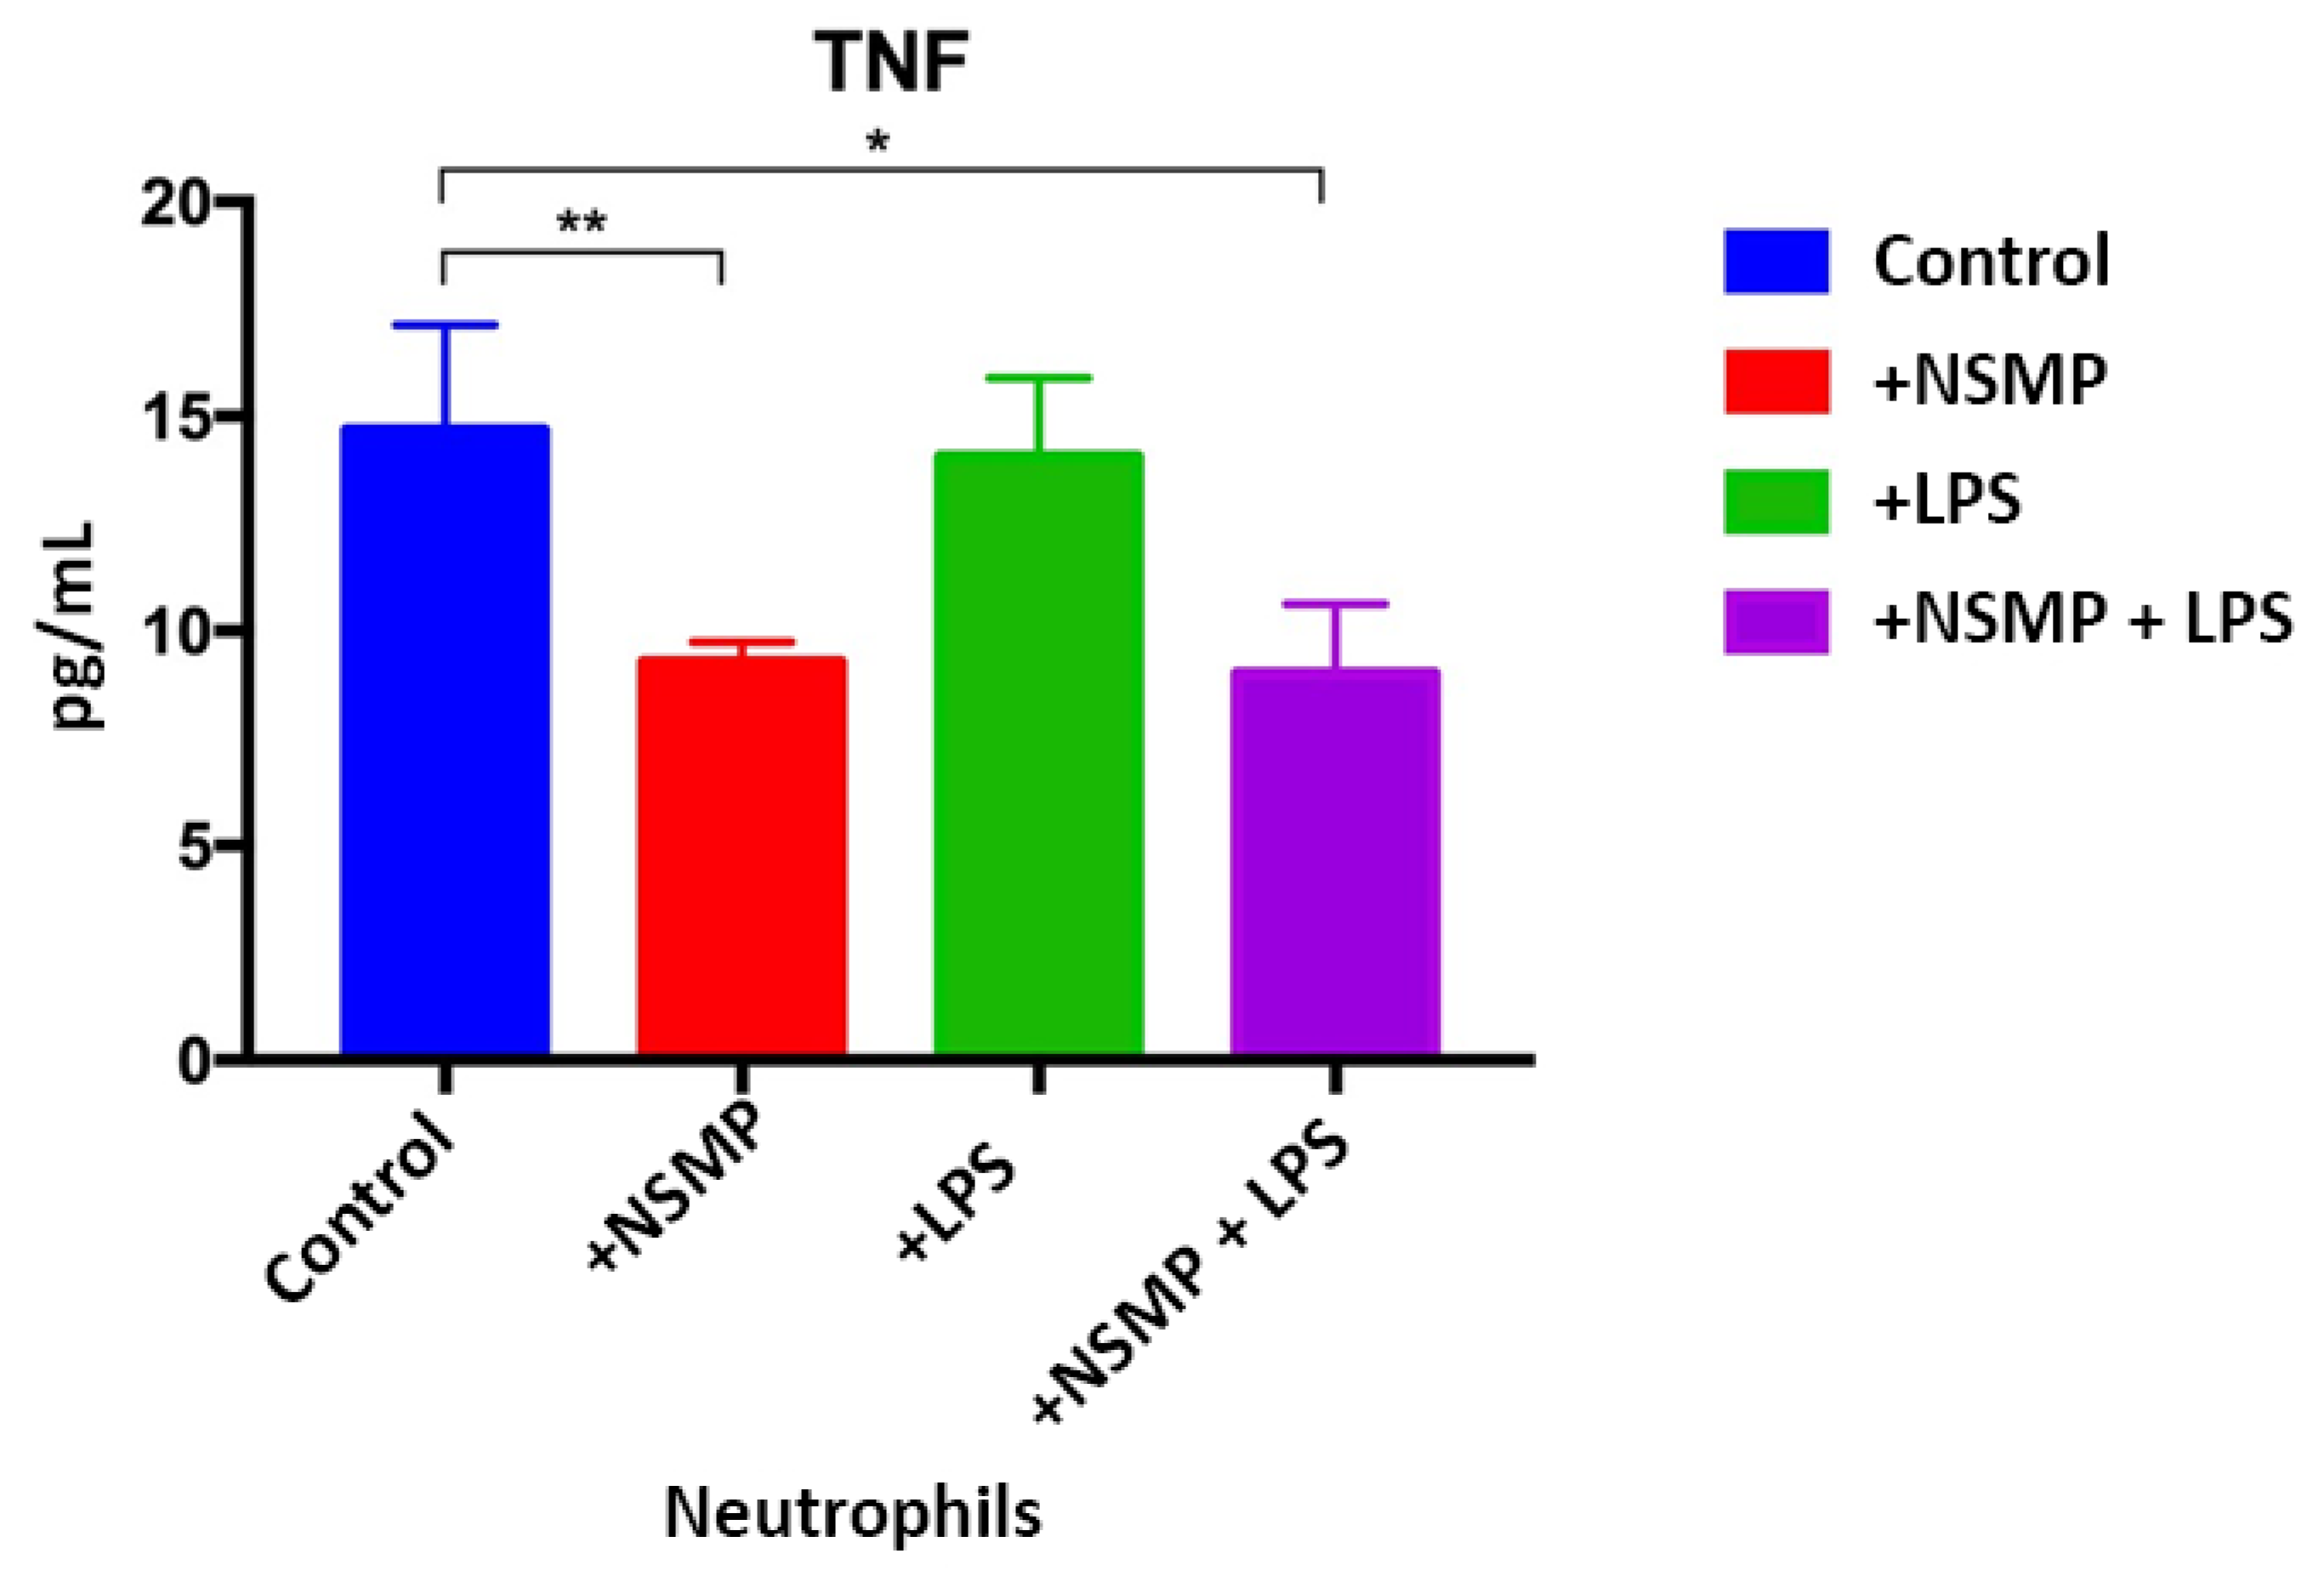

2.2. Results of Cytokine Production Studies, When Co-Culturing NSMP with Inflammatory Peritoneal Cell Exudate Obtained in the Mice Model of C57Bl/6J Inbred Line

| Group 1 Peritoneal Cellular Exudate Obtained on the First Day | Group 2 Peritoneal Cellular Exudate Obtained on the Third Day | ||||||

|---|---|---|---|---|---|---|---|

| Control 1 | Control 2 | Study 3 | Study 4 | Control 5 | Control 6 | Study 7 | Study 8 |

| Neutrophils (NP) | NP+ NSMP | NP+ LPS | NP+ LPS+ NSMP | Macrophages (MP) | MP+ NSMP | MP+ LPS | MP+ LPS+ NSMP |